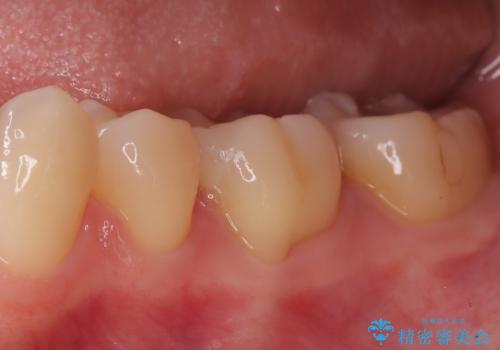

- 「銀歯を白くしたい」を主訴に来院された患者さんです。 左下6番に銀歯を被せてあり、一部分が欠けている状態でした。

銀歯と虫歯を除去しハイブリッドインレーで治療を行いました。

ハイブリッドインレーはセラミックと合成樹脂(プラスチック)が混ざったものです。従って経年劣化や色の変化はあるものの、保険適応の被せ物に比べ、セラミックの含有率が高く、型取りの材料もシリコン材を使用出来るので適合も優れています。